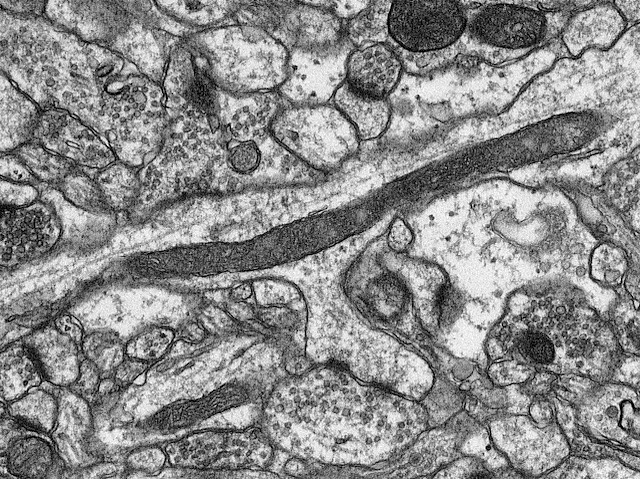

Rebent el Missatge

Les cèl·lules cerebrals (neurones) es comuniquen en les sinapsis, que són unions on es disparen missatges químics anomenats neurotransmissors cap als receptors de les neurones que estan a l'altre costat de l'espai que les separa. En esta micrografia electrònica, un tall del cervell d'un ratolí, veiem xicotetes bosses (anomenades vesícules) de neurotransmissors (estructures circulars en la part superior) llestes per a inundar la sinapsi (canal diagonal) cap als receptors que esperen (oval fosc) a l'altre costat. Els investigadors examinen imatges com esta per a investigar com les sinapsis es veuen afectades per malalties neurodegeneratives o mutacions genètiques. En esta regió cerebral en particular, l'hipocamp, perdre una proteïna anomenada importina β1, involucrada a preparar les vesícules, reduïx la comunicació neuronal. Això podria afectar l'aprenentatge i la memòria en l'hipocamp tant de ratolins com d'humans.